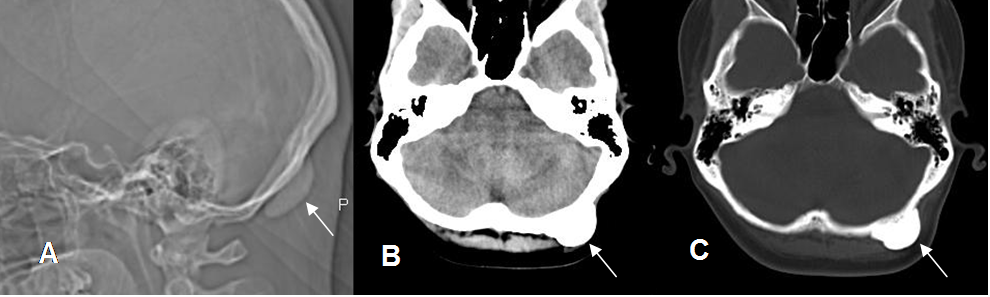

Fig 56. Osteoma.

A: Rx lateral, B: TAC axial en ventana de tejido y C: en ventana osea. Lesión ovalada y densa homogénea, a nivel occipital izquierdo, por osteoma.